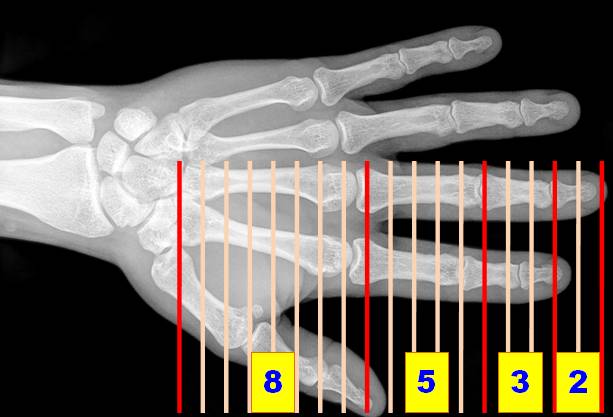

Degrés de liberté (DOF: Degrees of Freedom)

Degrés de liberté de la main

27 (ou 28) degrés de liberté ou possibilité de mouvement de la main et du poignet (dont 23 représentés sur figure de droite)

*       16 avec 4 pour chacun des quatre doigts: 3 en extension-flexion et 1 en abduction-adduction (aBduction: Mouvement qui écarte un membre, un segment de membre du plan médian du corps; aDduction: Mouvement qui rapproche de l'axe du corps);

*       5 degrés de liberté pour le pouce; et

*       6 degrés de liberté pour la rotation et la translation du poignet.

Détail (DOF = degrees of freedom)